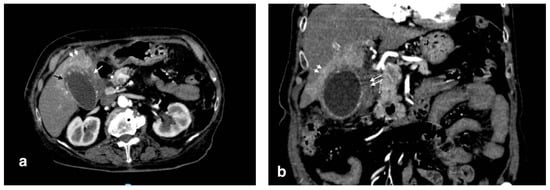

In the context of acute cholecystitis, the formation of liver abscess is an event strictly related to a gallbladder perforation. It can be differentiated in pericholecystic and parenchymal abscesses. The leakage of bile and other material from the gallbladder lumen can undergo infection (it could also be already infected) and finally organize in a mass, sometimes multiloculated, with a rounded contour and a more or less thick capsule, which can be collected in the pericholecystic space or, distally, in the liver parenchyma. Pericholecystic abscess as a complication of acute cholecystitis is reported in 3%–19% of cases [17]. The typical presentation consists in the evidence of intramural and pericholecystic rim-enhancing fluid collections, with the omentum often adherent/thickened (Figure 8). The abscess can be unilocular or have septations and an irregular contour [17]. Liver abscesses are classified by size: macroabscesses are more than 2 cm in diameter, and microabscesses are less than 2 cm in diameter [15]. Pathogenically, liver abscesses could also originate from an ascending infection from the biliary system [20]; in this case, MDCT reveals the presence of gallstones obstructing the biliary duct and/or suppurative cholangitis. After contrast injection, peripheral contrast enhancement is often shown (the so-called “rim sign”) (Figure 9). The presence of intralesional air is almost pathognomonic, despite being not always detectable.

Figure 9.

Liver abscess with pylephlebitis: (a) CT arterial phase; (b) CT portal phase. In the right lobe, V segment, a large hypodense collection with hypoattenuating halo due to intrahepatic abscess (black arrows, (a,b)) with the presence of a hypodensity within the left portal vein lumen due to thrombosis and hyperdensity of portal walls indicative of pylephlebitis better defined in CT portal phase (b) (white arrow).